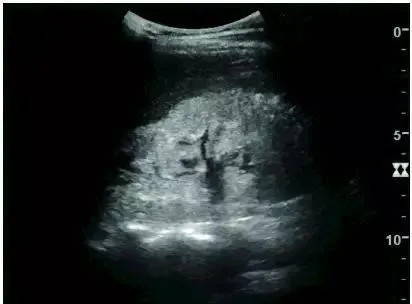

In patients with polycystic kidney disease, multiple cysts of varying sizes can be seen. In patients with advanced polycystic kidney disease, the kidneys are enlarged, with no obvious demarcation between cortex and medulla.

Advanced polycystic kidney disease with multiple renal cysts